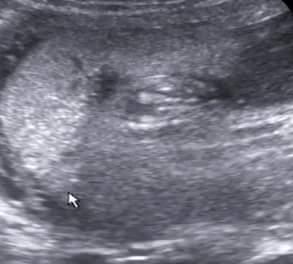

AHOJ, PRIKLADAM DVE FOTECKY ZE SCREENINGU.. OBE 13 + 1... PRVNI FOTO JE NAS DVOULETY CHLAPECEK.. JE VIDET VYBEZEK NAHORU, DRUHE FOTO , JE MIMINO, KTERE MAM TED V BRISKU.. DLE LEKARKY TO VYPADA NA HOLCICKU.. A JA ZATIM ASI MOHU SOUHLASIT..... NA DRUHE FOTCE VYBEZEK NAHORU NENI.... TAK OPET UVIDIME ZDA MI TO MA LEKARKA ZA TRI TYDNY POTVRDI...